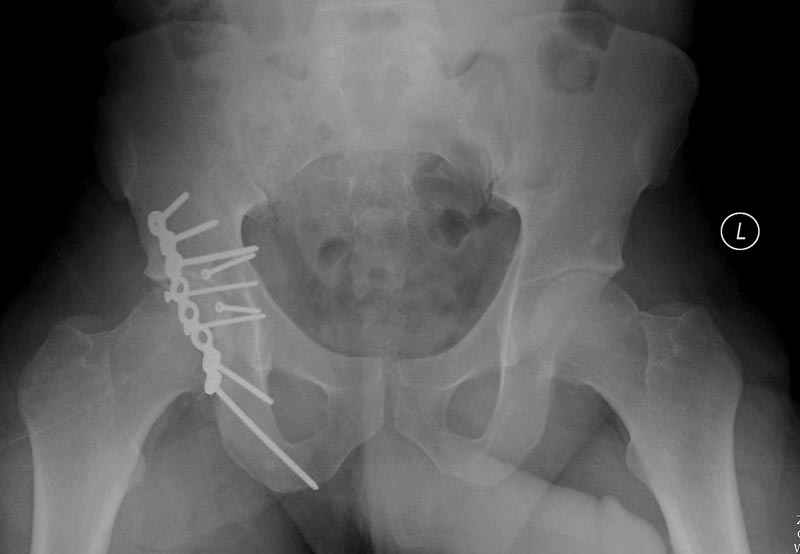

Выставлена на обсуждение (только одна проекция) рентгенограмма больного 25 лет, поступившего в приемное отделение, молодой дежурный врач сомневается в тактике лечения и спрашивает совета.

С его слов, больной стабилен,травму получил в результате автоаварии.Подскажите, что делать?Джолдас Кульджанов

5:24 Рентгенограмма таза, вызывают врача ортопеда (снимок N1), его диагноз: закрытый переломо-вывих правого тазабедренного сустава, получает добро на закрытую репозицию в приемном отделении

5:38 Дважды неудачная попытка закрытой репозиции в приемном отделении

N 2

6:20 ответстенный врач принимает решение о репозиции в условиях операционной, предупреждаются родственники и больной, что при неудачной закрытой репозиции, о возможности открытой репозиции и фиксации задней стенки вертлужной впадины.

7:30 начало операции, больной на спине, попытка репозиции после анестезии N3, укладка больного на боку, доступ Kocher- Langenbeck, состояние седалищнего нерва около 2.5см кровоподтек, через joistick головка бедра приподнята, освобовождение сустава, фрагмент заднего края более 3х4 см репонирован на свое место. После промывания

сустава, репозиция вывиха (N4), фиксация фрагмента 2.7(4) мм шурупами и допольнительно реконструктивной пластиной на 8 дырок, фиксация 3.5мм шурупами проксимально и дистально.

Интраоперционные N5 косая запирательная и N6 подвздошный снимок

11:50 больной в послеоперационной, рентгенограмма N7, компьютерная томограмма в тот же день N8-10